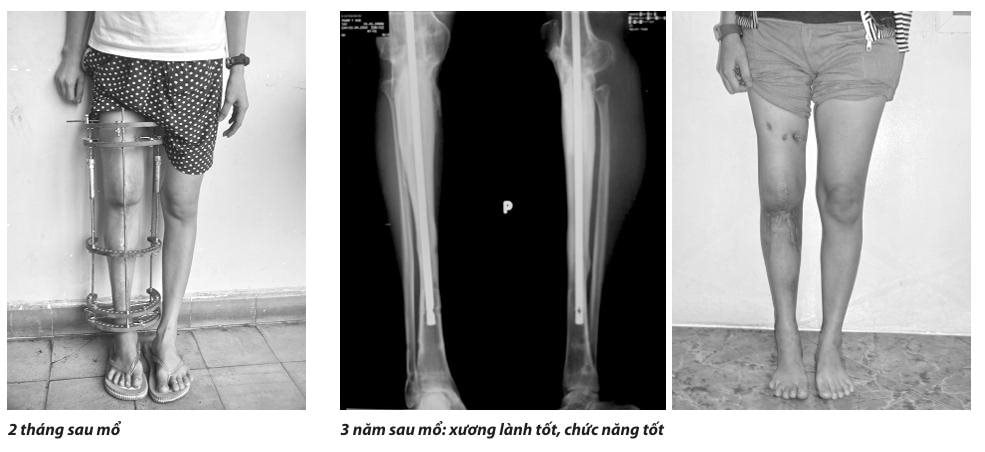

- Phẫu thuật tái tạo lại khuyết hổng sau khi cắt bướu có thể sử dụng một trong 2 phương pháp: (1) tái tạo sinh học (như ghép xương, kéo dài cal xương, ghép xương tự thân tái chế…) và (2) tái tạo cơ học (thay khớp nhân tạo megaprosthesis).

Từ đó đến nay, lĩnh vực này luôn được cải tiến, trở thành mũi nhọn phát triển của Khoa. Đã có nhiều luận văn thạc sĩ, chuyên khoa 2 và luận án tiến sĩ về phẫu thuật bảo tồn chi đã được bảo vệ thành công, góp phần vào sự phát triển chung của ngành bệnh học cơ xương khớp nói riêng và ngành y tế nói chung. Tuy nhiên, cho đến hiện nay chúng tôi chủ yếu vẫn sử dụng phương pháp tái tạo sinh học và chưa có điều kiện sử dụng phương pháp tái tạo cơ học (thay khớp megaprosthesis).

| Về lâu dài: khi đã lành xương, chi được bảo tồn sẽ đạt được sự vững chắc, bền vững, rất ít xảy ra biến chứng muộn | Kết quả thường tốt trong những năm đầu sau mổ. Về lâu dài: xuất hiện nhiều biến chứng muộn |

TS.BS Lê Văn Thọ, Trưởng khoa Bệnh học Cơ Xương Khớp, Bệnh viện Chấn thương Chỉnh hình TPHCM sinh năm 1968. Tốt nghiệp bác sĩ đa khoa tại ĐHYD TP.HCM năm 1994. Tốt nghiệp chuyên khoa 1, chuyên ngành Chấn thương chỉnh hình (CTCH) năm 1999. Tốt nghiệp Thạc sĩ Y học, chuyên ngành CTCH năm 2003. Bảo vệ luận án Tiến sĩ Y học, chuyên ngành CTCH năm 2011 với đề tài: “NGHIÊN CỨU BẢO TỒN CHI BẰNG PHƯƠNG PHÁP TẠO XƯƠNG KÉO DÃN THEO NGUYÊN LÝ ILIZAROV TRONG ÐIỀU TRỊ UNG THƯ XƯƠNG VÙNG GỐI”.